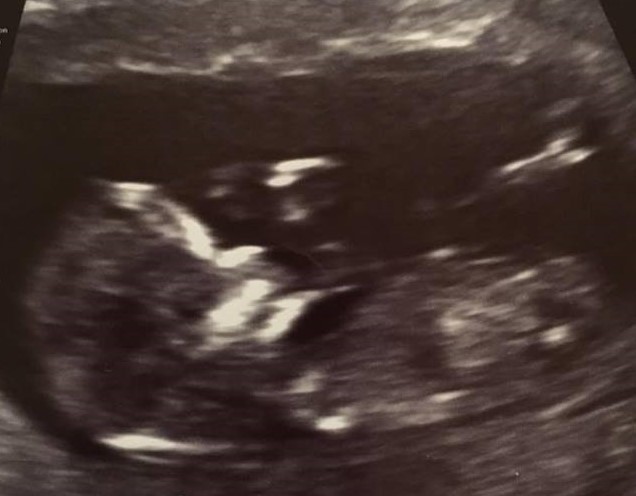

Hi, this is a friends nub and I'm intrigued to know what she might be having. People got her last one right :-)

12+1, is there a nub here?

I think I see a nub although it's not very clear... Maybe girl? Still time to rise though

I wasn't sure if there was one either, or if the line I can see is even a nub